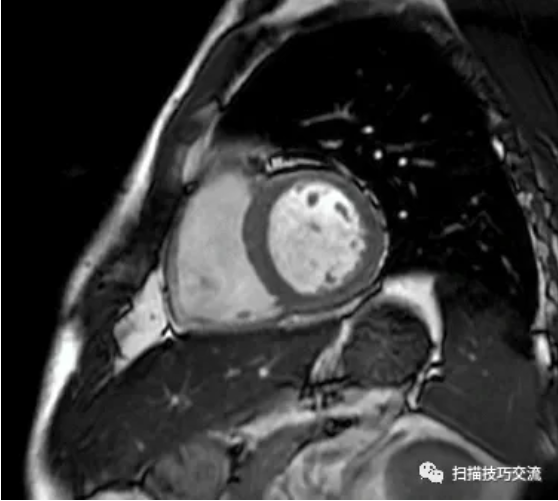

有人说,会不会是脂肪

FIESTA电影,收缩期末

FIESTA电影,舒张期末 相同位置,并未发现脂肪高亮信号。 补充病史: 一、 CTA提示:LCX中段90%狭窄。 这与磁共振的MDE序列相吻合。